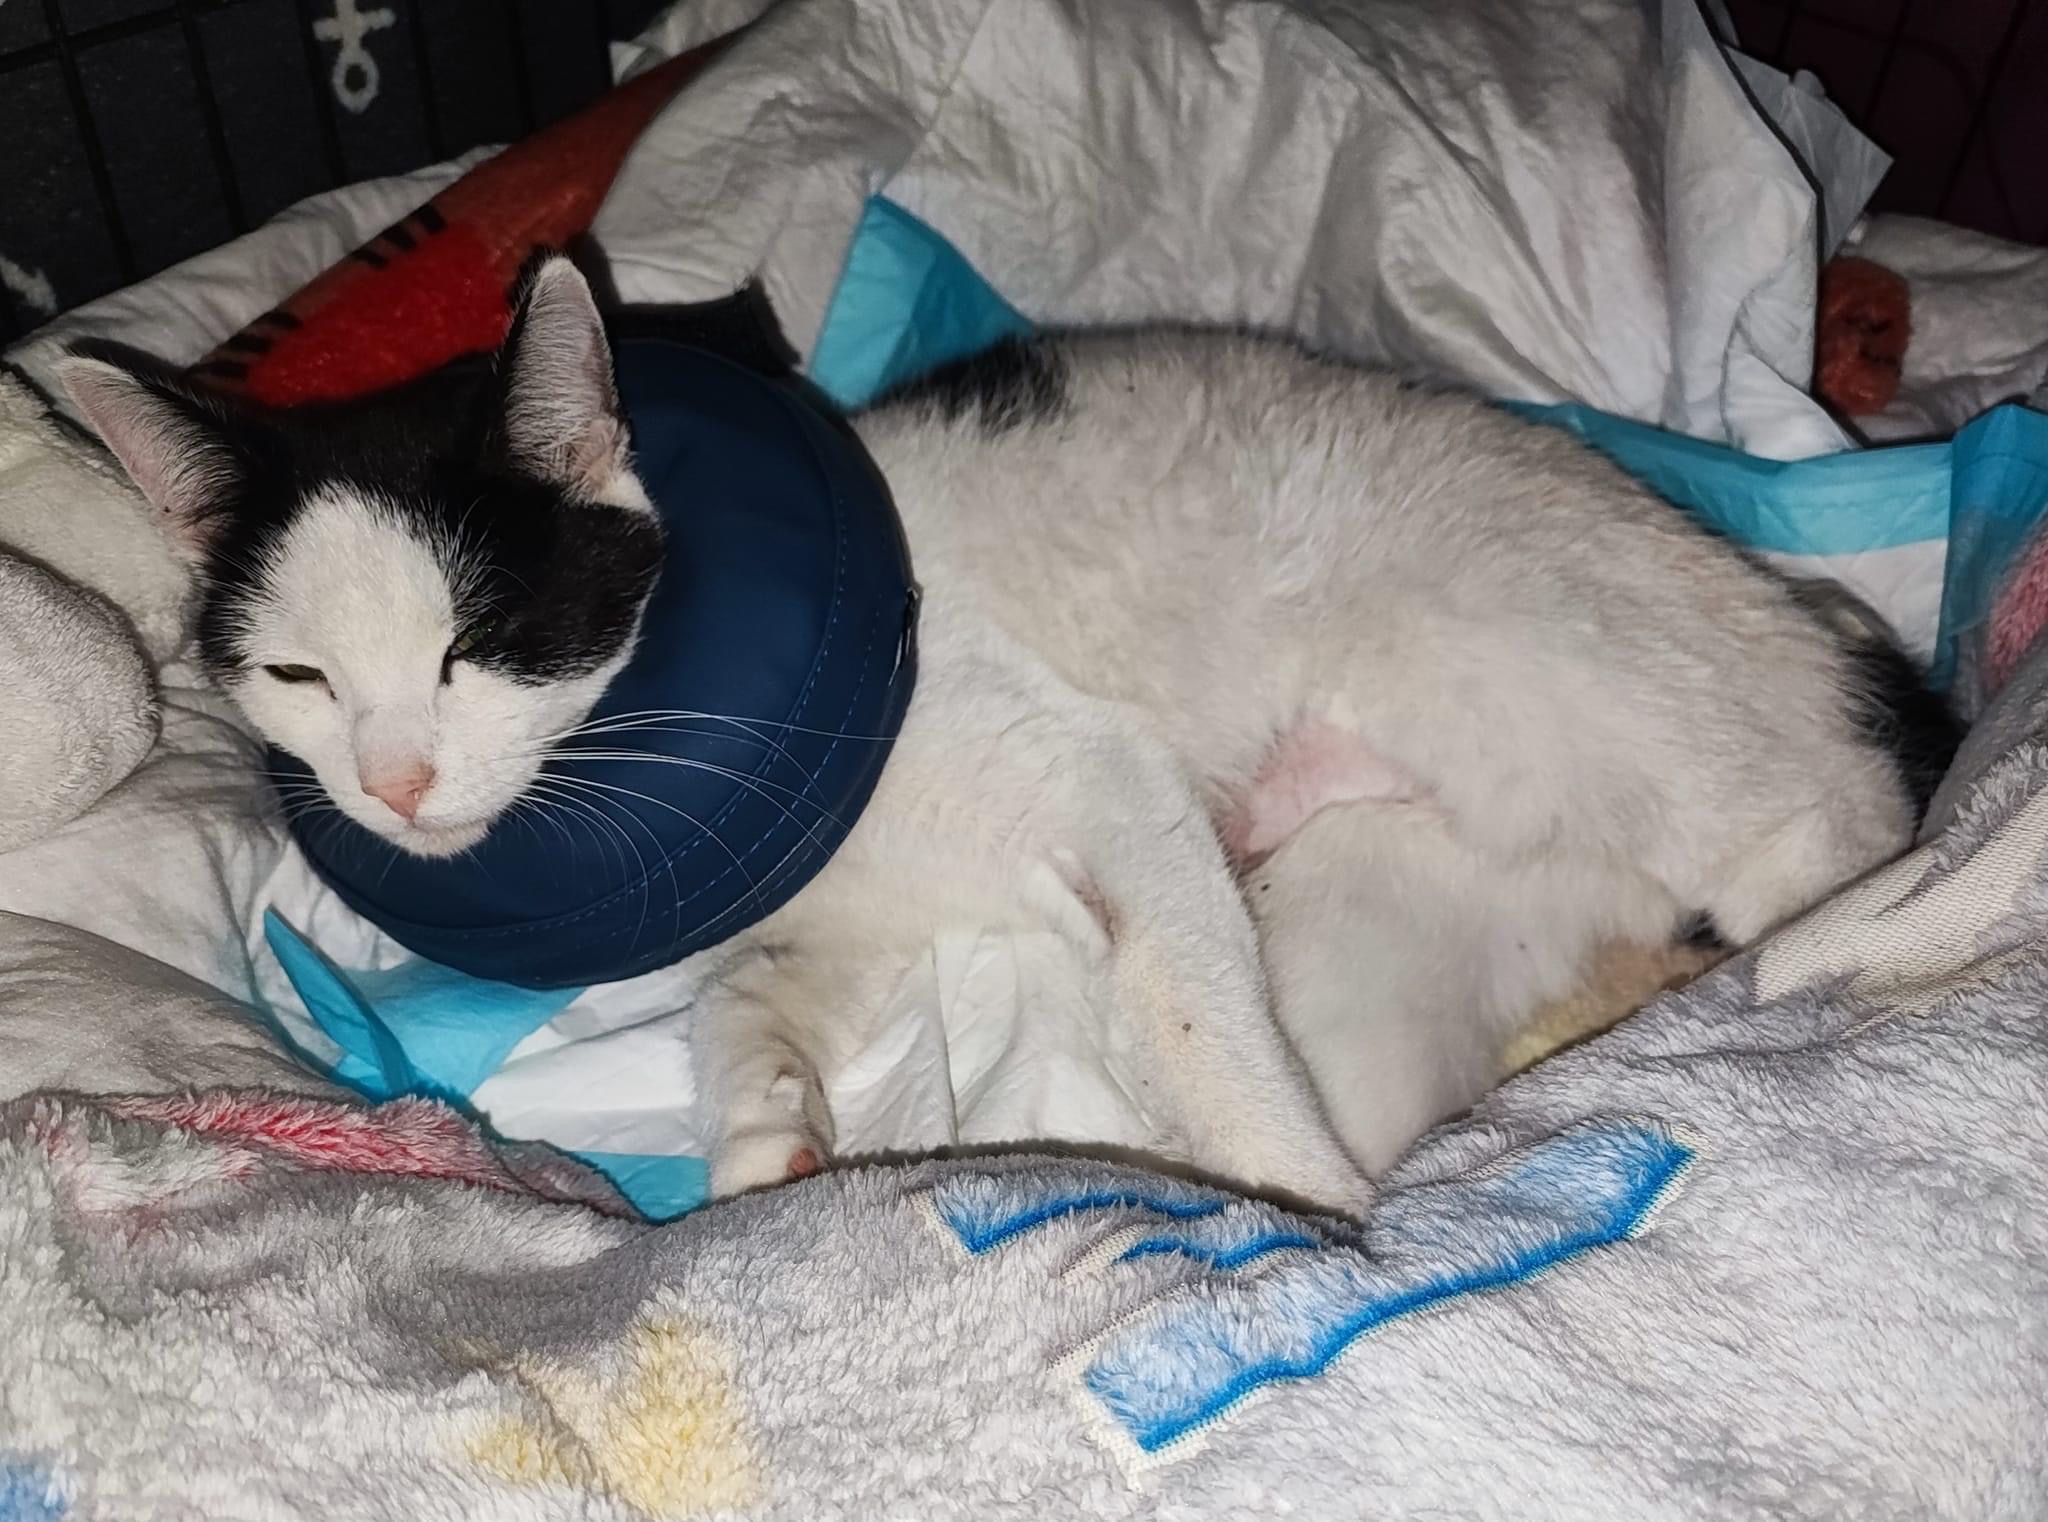

24.03.2023: Lucy ist zurück aus Berlin. Sie hat alles gut überstanden. Die OP war schon recht aufwendig. Die Tierärzte haben einiges geleistet an unserer Lucy. Beide Beckenknochen waren komplett ab und verschoben. Sie mussten wieder neu konstruiert und mit Schrauben fixiert werden. Sie hat noch einige Einblutungen in den Hinterbeinen, daher sind die Beine noch ziemlich angeschwollen. Das übernimmt ihr Körper aber wohl selbstständig und sollte sich in den nächsten Tagen geben. Sie bekommt jetzt in Ruhe ihre Medikamente und kann sich erholen.

25.03.2023: Unsere Lucy hat die erste Nacht gut überstanden. Sie hat gut geschlafen, hat heute Früh gepullert und gekackert. Zwar noch unter sich, weil sie noch nicht auf die Toilette gehen kann aber es funktioniert alles. Gegessen hat sie super und das Reconvales mag sie sehr. Ihre Wunde sieht noch sehr geschwollen aus, aber das wird besser in den nächsten Tagen. Alles in allem sind wir sehr zufrieden.